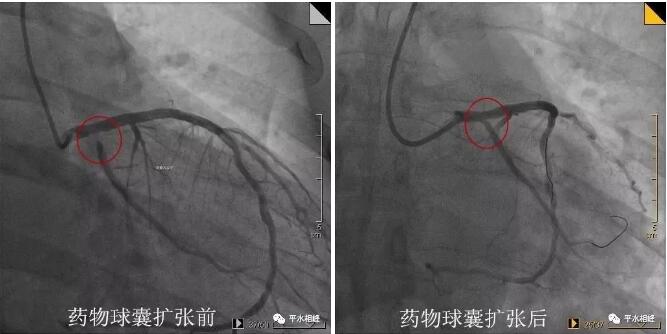

病例一 53岁中年男性,胸闷不适1月入院。1年前曾行支架植入术,复查冠脉造影提示支架内再狭窄。于支架内行药物球囊扩张术,术后效果良好。 病例二 69岁老年男性,突发胸痛1.5小时入院。既往有高血压、糖尿病病史。反复冠脉造影提示回旋支开口较前狭窄加重,行药物球囊扩张术,术后未再发作胸痛。 病例三 53岁中年男性,发作性胸部不适1月入院。新发现高血压、糖尿病。冠脉造影提示第一对角支粗大,开口狭窄80%,行药物球囊扩张术,术后效果良好。 什么是药物球囊扩张术 据高希春主任医师介绍,药物涂层球囊(DCB),是在传统球囊上基础上,均匀地涂上紫杉醇和造影剂(碘普罗胺)的混合基质,医生用30~45秒的时间扩张球囊,把药物贴粘至心脏冠状动脉的病变部位,起抗细胞增殖的作用,然后球囊和导管撤出体外,患者体内不留任何异物。 与目前治疗冠心病的主要临床手段--药物支架相比,药物球囊具有显著优势: ①在完成对病变血管的治疗后撤出体外,不留在人体内,能大大减轻血管内膜炎症反应,同时有效维持血管正常解剖结构,为患者保留必要的后续治疗机会。 ②没有支架的Polymer聚合物基质,同时无金属网格残留,在人体内不留异物,可明显减少血栓发生率,可将患者服用双联抗血小板凝聚药物的时间由药物支架的12个月以上缩短到1~3个月,可极大地降低患者出血的风险。 但并不是所有患者适合药物球囊,药物球囊主要适用于某些分叉病变、支架内再狭窄、小血管病变、弥漫性病变等药物支架疗效不佳或无法治疗患者。 药物球囊扩张技术以前只能在三甲及以上医院开展。随着药物涂层球囊技术在我院的开展,避免了患者必须转诊至市级以上大医院才能完成该手术的困境。 【科室简介】 心内科二病区目前共有医护人员23人,其中主任医师1名,副主任医师2名,主治医师6名,住院医师1名,其中硕士学历6人。科室擅长冠心病及其介入诊疗,心律失常及永久起搏器植入术,心内科常见疑难危重病例的诊治。 医院心内科介入团队2018年共完成冠脉造影+支架植入术1600多例,急诊PCI近二百例,均取得良好效果。 心内科二病区位于住院部五楼西区 护士站电话:0533-8228195 医生办公室:0533-822882